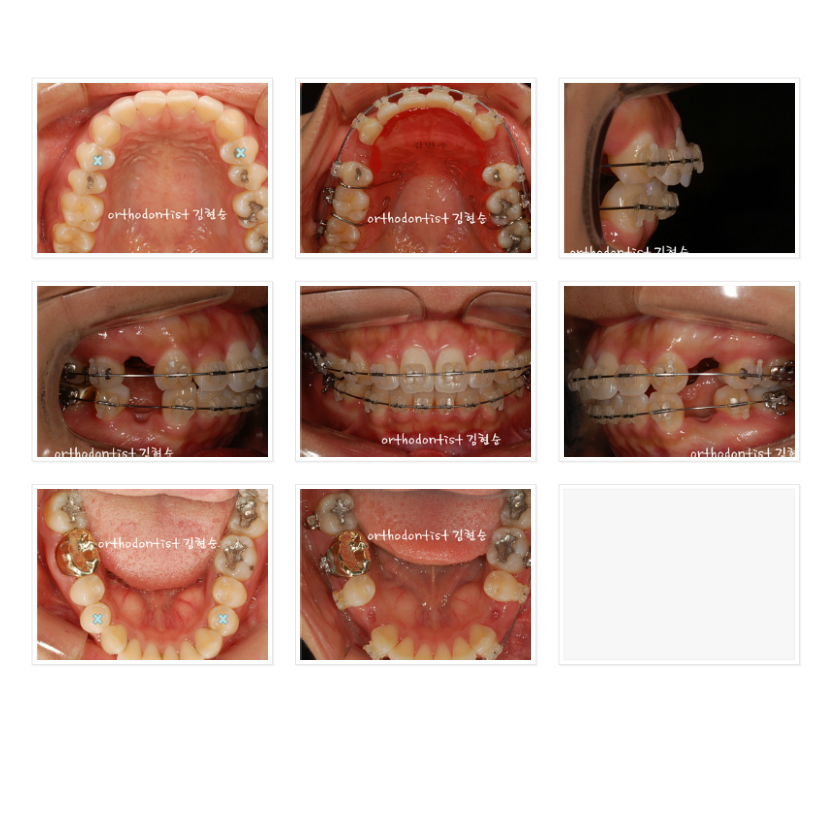

이 분은 앞 얼굴 및 전체적인 인상이 정말 아름다워지셨습니다.

다만 공개된 곳에서 정면 얼굴을 올리시는 것은 결례인 것 같아

차마 올리지 못해 아쉽네요.^^;